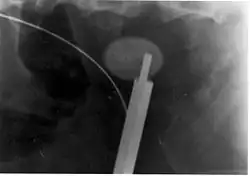

A kidney stone at the tip of an ultrasonic stone disintegration apparatus

More definitive ureteroscopic techniques for stone extraction (rather than simply bypassing the obstruction) include basket extraction and ultrasound ureterolithotripsy. Laser lithotripsy is another technique, which involves the use of a holmium:yttrium aluminium garnet (Ho:YAG) laser to fragment stones in the bladder, ureters, and kidneys.[118]